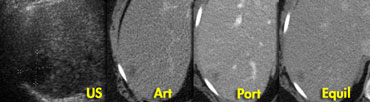

Small hemangioma atypical on US, showing typical enhancement of small hemangioma on CT. Small hemangioma atypical on US, showing typical enhancement of small hemangioma on CT.

On the left an atypical hypoechoic lesion, surrounded by a small but definite halo.

In the arterial phase there is homogeneous enhancement of arterial intensity, frequently seen in small hemangiomas.

In the portal venous phase and in the equilibrium phase it has the same enhancement as the aorta.

So all appearances are consistent with a hemangioma, a benign, non-solid vascular lesion.